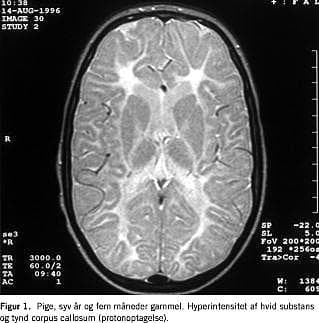

En grundig neurometabolisk screening viste normale resultater af følgende undersøgelser: urinaminosyrer og organiske syrer, lysosomale enzymaktiviteter, kreatinkinase, myoglobin, carnitin, acetylkolinreceptorantistoffer, nerveledningshastighed, muskelbiopsi (inkl. elektronmikroskopi), meget langkædede fede syrer, fytansyre, laktat og pyrovat. Der var ingen vakuoliserede lymfocytter otte måneder gammel (lysmikroskopi). Oftalmoskopi, audiometri, hjernestammeaudiometri og CT af cerebrum var normale. Initialt var elektroencefalografi (EEG)-værdierne normale, men da pigen var 7 år gammel, viste EEG diffus lavfrekvent aktivitet (2-3Hz) og et spike-focus. En MR-skanning af cerebrum viste omfattende mangel på myelinisering i de cerebrale hemisfærer, manglende myelinisering af cerebellum og en tynd corpus callosum og hjernestamme (Figur 1 ). Vermix cerebellum var udtalt atrofisk, og der fandtes nogen atrofi af cerebrum (Figur 2 ).

Ved SS er symptomerne bl.a. psykomotorisk retardering og ataksi, og ved MR af cerebrum ses hyperintensitet af den subkortikale hvide substans i cerebrum og hypoplasi af corpus callosum [1-3]. Børnenes klinik og MR-fund var forenelige med SS. Der er sammenhæng mellem genotype og fænotype, således har homozygote for den finske mutation et mildere forløb, mens compound heterozygote, som de danske børn, ofte har et sværere forløb og tilsvarende mere udtalte forandringer ved MR af cerebrum [4, 5]. Nonsense -mutationen er tidligere beskrevet hos en svensk patient [4].